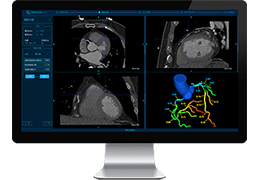

View X-Ray CT & MRI Scans Fast and Easily

Designed for surgeons, Pro Surgical 3D makes it easy to view patient scans quickly. Pro Surgical 3D facilitates the optimal 3D treatment and assessment workflows based on X-ray CT and MRI scans – and best of all, it’s FREE!

Traditional multi-planar slicing

High-quality and fast 3D reconstruction and 3D rendering

Performs 3D reconstruction and volume rendering.

Multi-planar slicing.